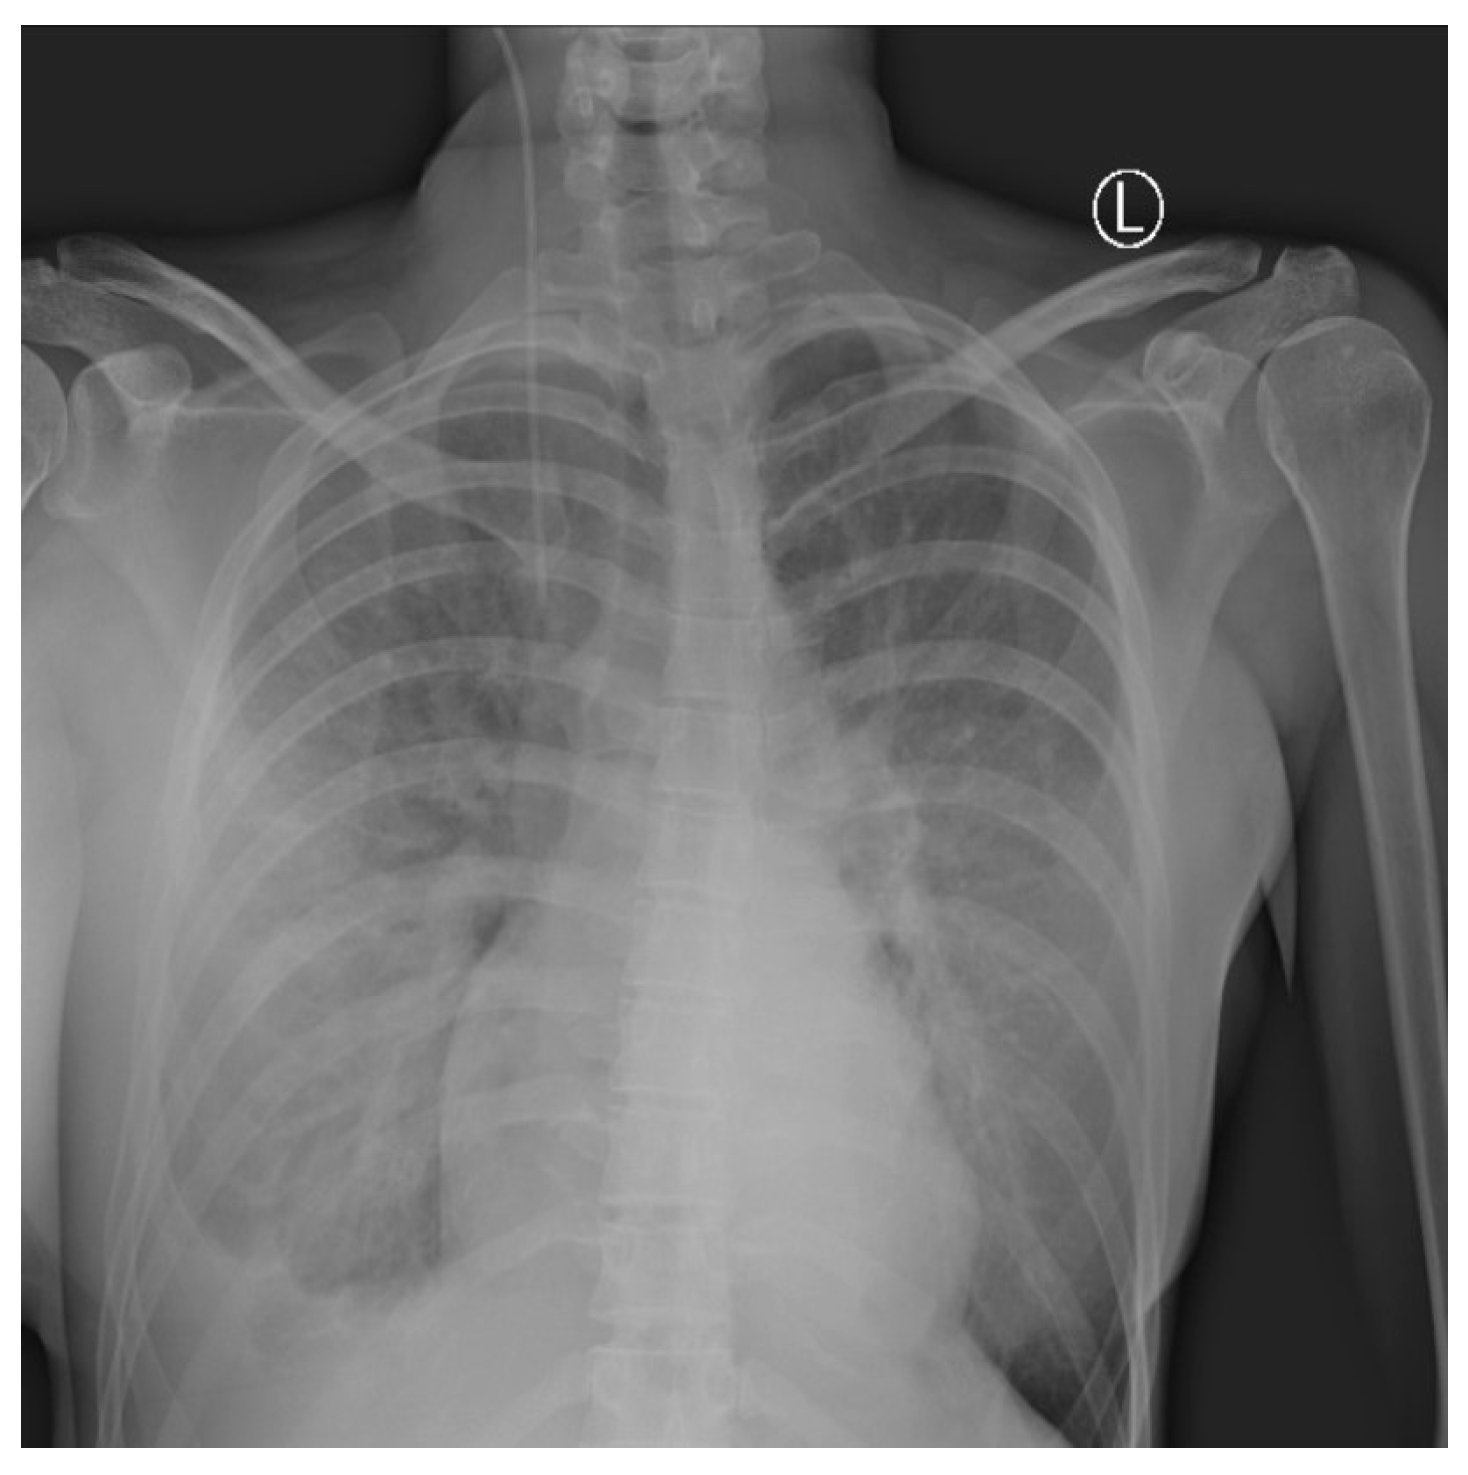

Daily surgical debridement and drainage were performed, and control of the infection was obtained. Regardless of the improvement of the NSTI, in the following days, the respiratory symptoms worsened in terms of dyspnea, with peripheral blood oxygen level measured at 88%. Oxygen therapy was administered with maximum oxygen flow up to 12 L/min, leading to control of oxygen saturation of 96%. A chest radiography revealed signs of progressive bilateral pneumonia with a right-sided pleural effusion (Figure 4). High fever with high-inflammation blood markers persisted hence the antimicrobial therapy was corrected. Tigecycline, Metronidazole, and Fluconazole were administered.

Figure 4.

Chest X-ray shows right-sided pleural effusion with bilateral lung interstitial thickening. The interpretation of the image was partially limited due to superposition of breast implants.